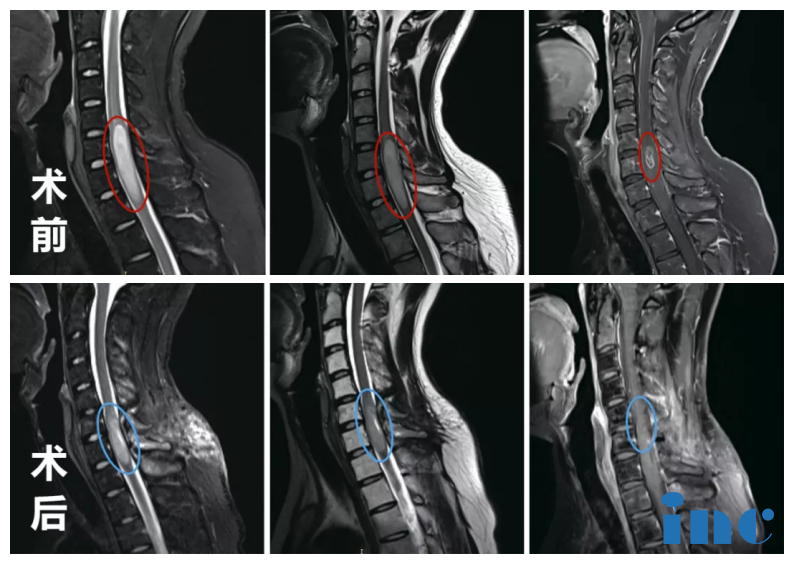

2、脊髓內(nèi)腫瘤

簡(jiǎn)要病史:30歲白領(lǐng)林先生,頸痛、手臂麻木持續(xù)半年,一經(jīng)檢查發(fā)現(xiàn)“占位性脊髓病變”,后病理活檢確診為“髓內(nèi)星形細(xì)胞瘤”,手術(shù)造成殘疾的可能性大,很多醫(yī)生保守治療

INC國(guó)際教授遠(yuǎn)程評(píng)估意見(jiàn):委托國(guó)外親戚查資料等最后找到INC德國(guó)巴特朗菲教授,得到教授回復(fù)大意為:考慮到腫瘤有H3F3A K27M基因突變,并且有MGMT非甲基化,化療不合適。建議病人接受二次手術(shù), 目的是盡可能多地減瘤(減少腫瘤體積到程度, 因?yàn)檫@種腫瘤完全切除是不可能的),術(shù)后,建議輔助免疫治療等其他手段。

脊髓內(nèi)腫瘤——腦瘤治療案例

INC國(guó)際教授主刀手術(shù)后:巴教授為他行髓內(nèi)占位全切術(shù)、頸5-6椎體成行術(shù)。術(shù)后MRI顯示:脊髓內(nèi)星形細(xì)胞瘤瘤體強(qiáng)化部分被完整切除,腫脹效應(yīng)減輕。術(shù)后一天,醫(yī)院給予頸部外固定護(hù)理,患者意識(shí)清醒;術(shù)后4天可以下地行走。術(shù)后10天,出院回國(guó)進(jìn)行康復(fù)護(hù)理和后續(xù)治療。

脊髓內(nèi)腫瘤案例——腦瘤治療案例